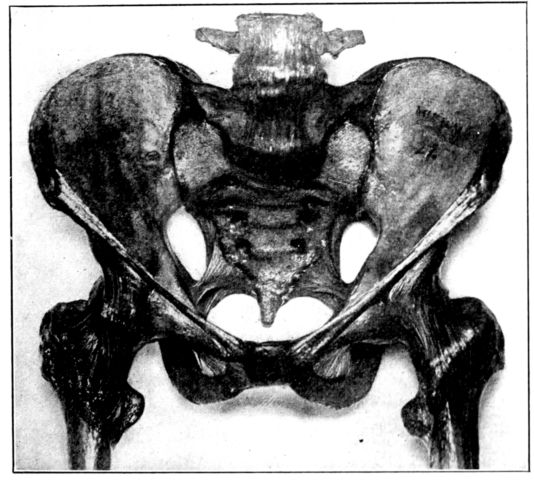

Viewed in its entirety, the pelvis is an irregularly constructed, two-storied, bony cavity, or canal, situated below and supporting the movable parts of the spinal column, and resting upon the femora or thigh bones. (Fig. 1, A. and B.).

Four bones enter into the construction of the pelvis: the two hip bones or ossa innominata, on the sides and in front with the sacrum and coccyx behind.

The innominate bones (ossa innominata), symmetrically placed on each side, are broad, flaring and scoop-shaped. Each bone consists of three main parts, which are separate bones in early life, but firmly welded together in adults: the ilium, ischium and pubis. The ilia are the broad, thin, plate-like sections above, 20their upper, anterior prominences, which may be felt as the hips, are the anterior superior spinous processes used in making pelvic measurements. The margins extending backward from these points are termed the iliac crests.

The ischii are below and it is upon their projections, known as the tuberosities, that the body rests when in the sitting position, and which also serve as landmarks in pelvimetry. The pubes form the front of the pelvic wall, the anterior rami uniting in the median line by means of heavy cartilage and forming the symphysis pubis.

The sacrum and coccyx behind are really the termination of the spinal column, the sacrum consisting, usually, of five rudimentary vertebrae which have fused into one bone. It sometimes consists of four bones, sometimes six, but more often of five. The sacrum completes the pelvic girdle behind by uniting on each side with the ossa innominata by means of strong cartilages, thus forming the sacro-iliac joints. The spinal column rests upon the upper surface of the sacrum. The coccyx, a little wedge-shaped, tail-like appendage, which ordinarily has but slight obstetrical importance, extends in a downward curve from the lower margin of the sacrum, to which it has a cartilaginous attachment, the sacro-coccygeal joint. This joint between the sacrum and coccyx is much more movable in the female than in the male pelvis.

We find, therefore, that although the pelvis constitutes a rigid, bony, ringlike structure, there are four joints: the symphysis pubis, the sacro-coccygeal, and the two sacro-iliac articulations. As the cartilages in these joints become somewhat softened and thickened during pregnancy, because of the increased blood supply, they all permit of a certain, though limited amount of motion at the time of labor. This provision is of considerable obstetrical importance, since the sacro-coccygeal joint allows the child’s head to push back the forward-protruding coccyx, as it passes down the birth canal, thus removing what otherwise might be a serious obstruction. And when, as is sometimes necessary, because of a constricted inlet, the pubic bone is cut through (the operation known as pubiotomy), the hingelike motion of the sacro-iliac joint permits of an appreciable spreading of the two hip bones and a consequent widening of the birth canal.

A. Normal female Pelvis.

B. Normal male Pelvis.

Fig. 1.—Normal Pelves. Note the broad, shallow, light construction of the female pelvis, A, as compared with the more massive male pelvis, B.

The normal male pelvis is deep, narrow, rough and massive as compared with the female structure (see Fig. 1.), and the angle of the pubic arch, formed by the two pubic bones, is deeper and more acute in the male than in the female skeleton.

The normal female pelvis, on the other hand, is light, broad, shallow, smooth and large, giving evidence of the infinite wisdom and skill that entered into constructing it for the high purpose it was designed to serve.